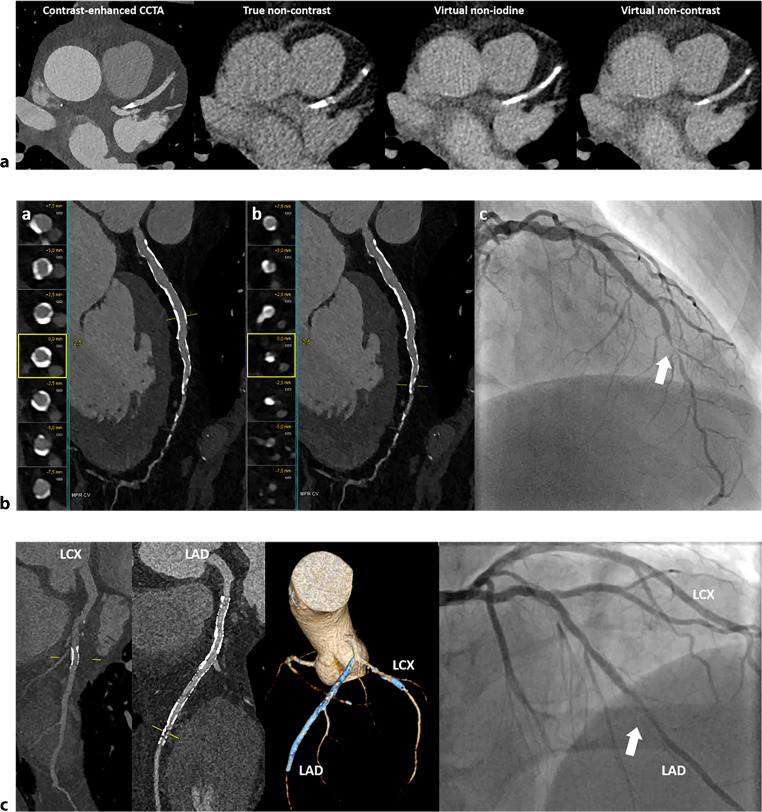

Photon-counting detector computed tomography (PCD-CT) has emerged as a revolutionary technology in CT imaging. PCD-CT offers significant advancements over conventional energy-integrating detector CT, including increased spatial resolution, artefact reduction and inherent spectral imaging capabilities. In cardiac imaging, PCD-CT can offer a more accurate assessment of coronary artery disease, plaque characterisation and the in-stent lumen. Additionally, it might improve the visualisation of myocardial fibrosis through qualitative late enhancement imaging and quantitative extracellular volume measurements. The use of PCD-CT in cardiac imaging holds significant potential, positioning itself as a valuable modality that could serve as a one-stop-shop by integrating both angiography and tissue characterisation into a single examination. Despite its potential, large-scale clinical trials, standardisation of protocols and cost-effectiveness considerations are required for its broader integration into clinical practice. This narrative review provides an overview of the current literature on PCD-CT regarding the possibilities and limitations of cardiac imaging.